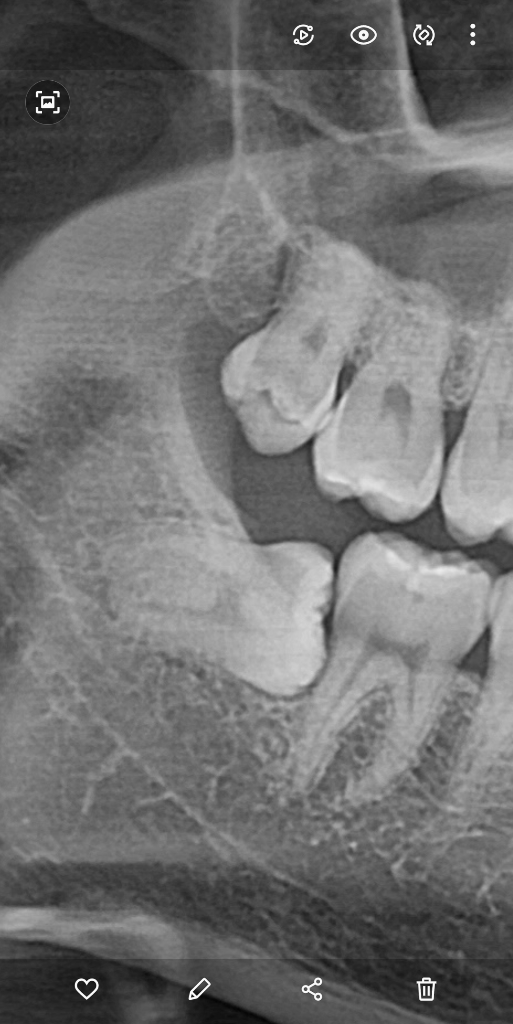

여기 사랑니를 발치하게 되면

어금니가 흔들리게 되고

결국 뽑게 될까 걱정입니다

사랑니를 발치 후

그 옆에 뼈가 차오르고

어금니가 흔들리지 않고 잘 치유가 될 수 있나요???

그렇게 될 가능성은 낮아 보입니다. 염증이 많으신것도 아니니 사랑니 발치하고 나면 어느정도 치조골이 회복될껏같습니다. 발치하고 나셔서 그쪽에 염증이 생기지 않도록만 하시면 문제 없을것같네요.

해당 사랑니를 제거하더라도 앞쪽 치아는 흔들리지 않으며 뼈도 자연스럽게 차오릅니다. 현재 사진은 2차원적인 것이며 사랑니를 발치하더라도 앞쪽에 치아는 3면이 모두 뺘로 덮여 있고 뒤쪽만 남아 있기 때문에 해당 부위는 주변 조직의 신호 등에 의해서 자연스럽게 뼈가 차오르고 회복됩니다. 따라서 크게 걱정하지 않아도 됩니다.